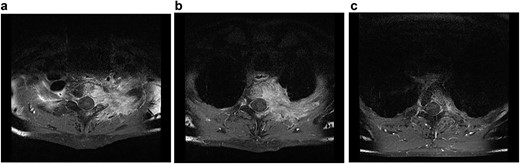

Despite the definitive chemoradiation therapy, a locally progressive tumor without evidence of distant metastasis was detected 2 months later in an MRI associated with the infiltration of Th1–3 and invasion of the first and second left thoracic root without evidence of a myelon compression (Figs 1 and 2).

Transversal MRI STIR-images of patient No. 2 with Th1 (a), Th2 (b) and Th3 (c).